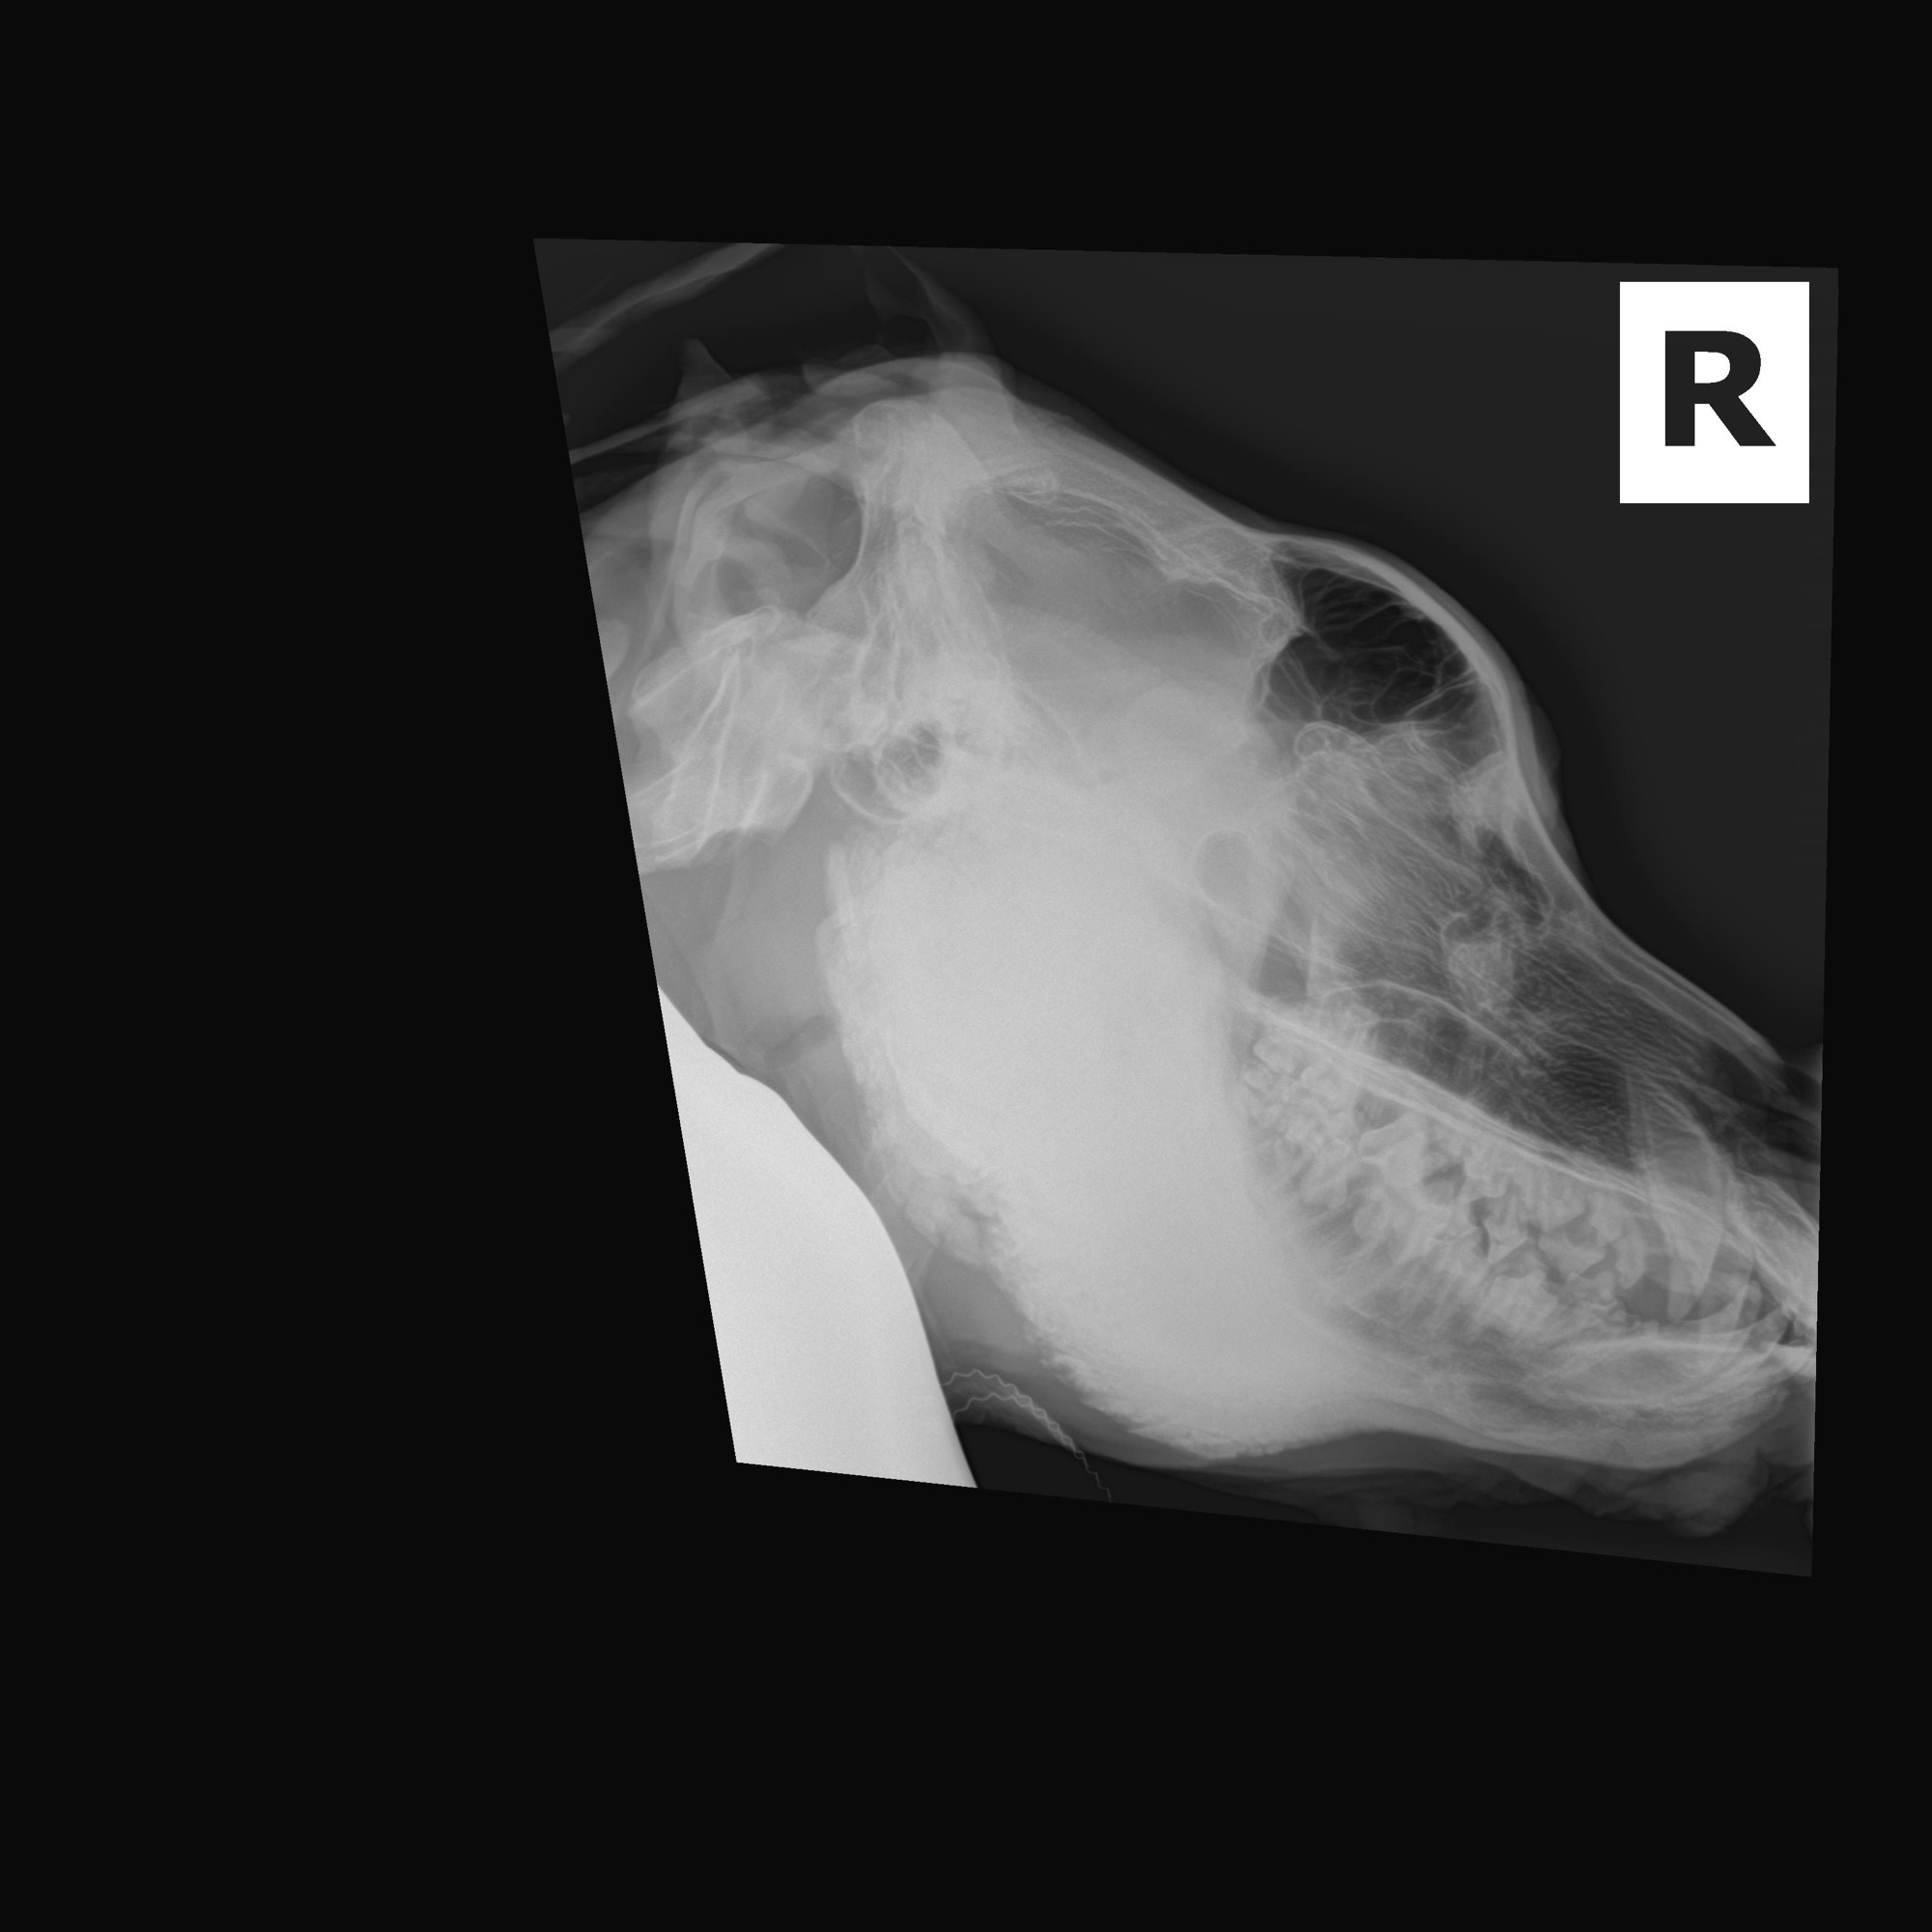

Meet Fred. We are estimating him to be about a year old (DOB 7/1/24). Fred came to us in extremely poor shape in part due to an uncommon disease, craniomandibular osteopathy (CMO). CMO caused extra bone growth in Fred skull and mandible as well as his front legs. He does have signs of CMO in other limbs as well however they are not as prolific as his skull/mandible and front legs.

Fred was vetted at The University of Florida and they confirmed his condition after a CT scan and full body radiographs.